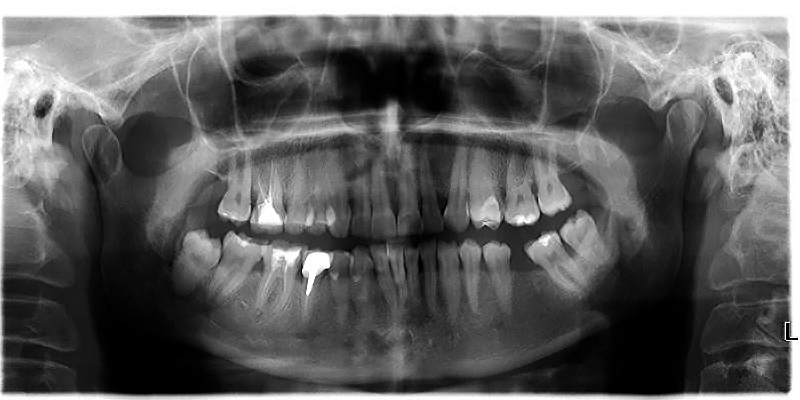

Ne-am concentrat mereu pe a oferi un serviciu de cea mai buna calitate in conditii accesibile. In acelasi timp, evitam pe cat de mult sa pierdem din timpul pacientilor nostri, redirectionandu-i pentru investigatii suplimentare. Avem deja mijloacele de investigatie la noi in clinica. Fie ca ai nevoie de o radiografie simpla sau panoramica, de tratament la microscop, consultatie ortodontica sau interventie chirurgicala, noi te putem ajuta. Am ales cu atentie medicii cu care colaboram, ei fiind nu doar specialisti de exceptie dar si oameni in adevaratul sens al cuvantului.

Avem deja mijloacele de investigatie la noi in clinica. Fie ca ai nevoie de o radiografie simpla sau panoramica, de tratament la microscop, consultatie ortodontica sau interventie chirurgicala, noi te putem ajuta. Am ales cu atentie medicii cu care colaboram, ei fiind nu doar specialisti de exceptie dar si oameni in adevaratul sens al cuvantului. Ne-am facut un renume din a avea grija de copii si dintisorii lor problematici. I-am primit pe toti cu rabdare, atentie si blandete si cu multe sfaturi bune pentru parintii lor. Ne-am daruit cu totul profesiei noastre si am venit in intampinarea pacientilor nostri cu un program flexibil si adaptat nevoilor lor. Vrem sa continuam sa ne raspandim filozofia noastra. Sa tratam oamenii omeneste, profesionist dar si cu rabdare si intelegere. Stim ca este un succes si ne vom incapatana sa credem ca viitorul medicinei este tratamentul adaptat fiecarei nevoi si mai ales fiecarui om in parte.